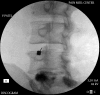

Figure 24.

Figure 24.. A, B, C and D: Spinal Cord stimulator Lead Placement for Low Back Pain as Well as Radicular Pain in a Post-Laminectomy Pain Patient Using a Dual Lead Configuration

The lesion is generated between the tips of the probes and provides a near complete coverage of the posterior annulus.